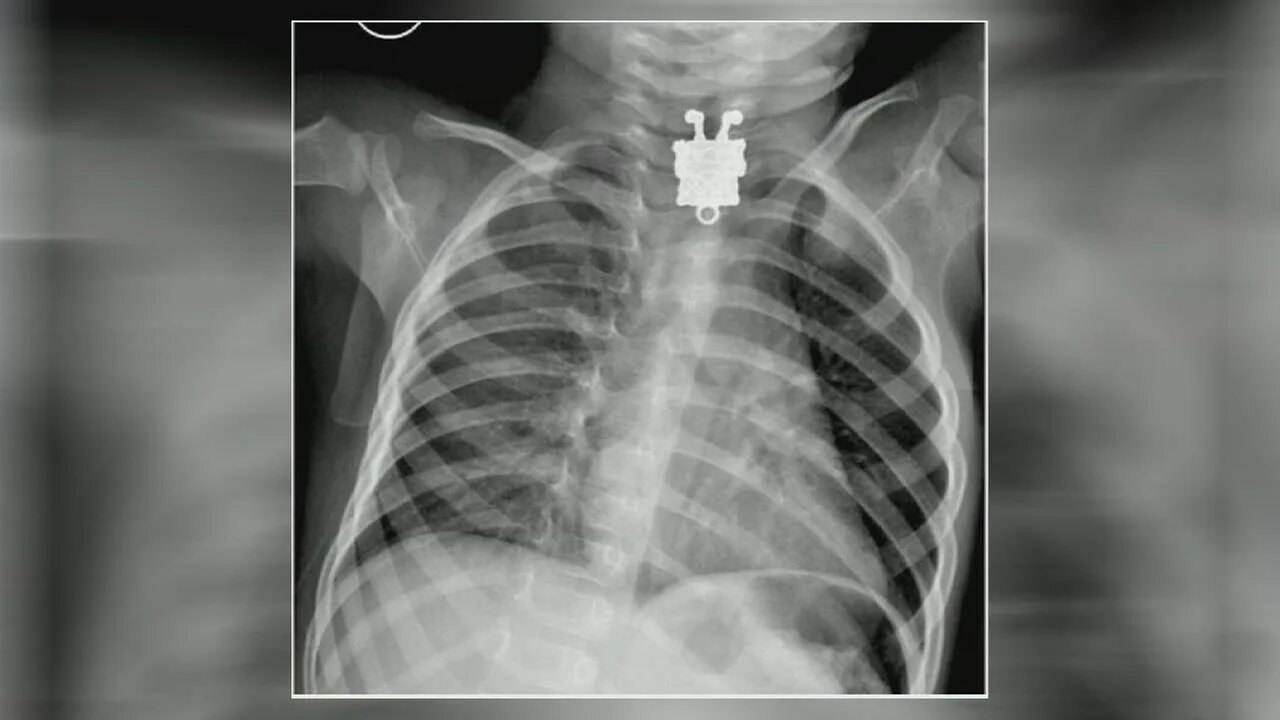

Как узнать проглотил ребенок